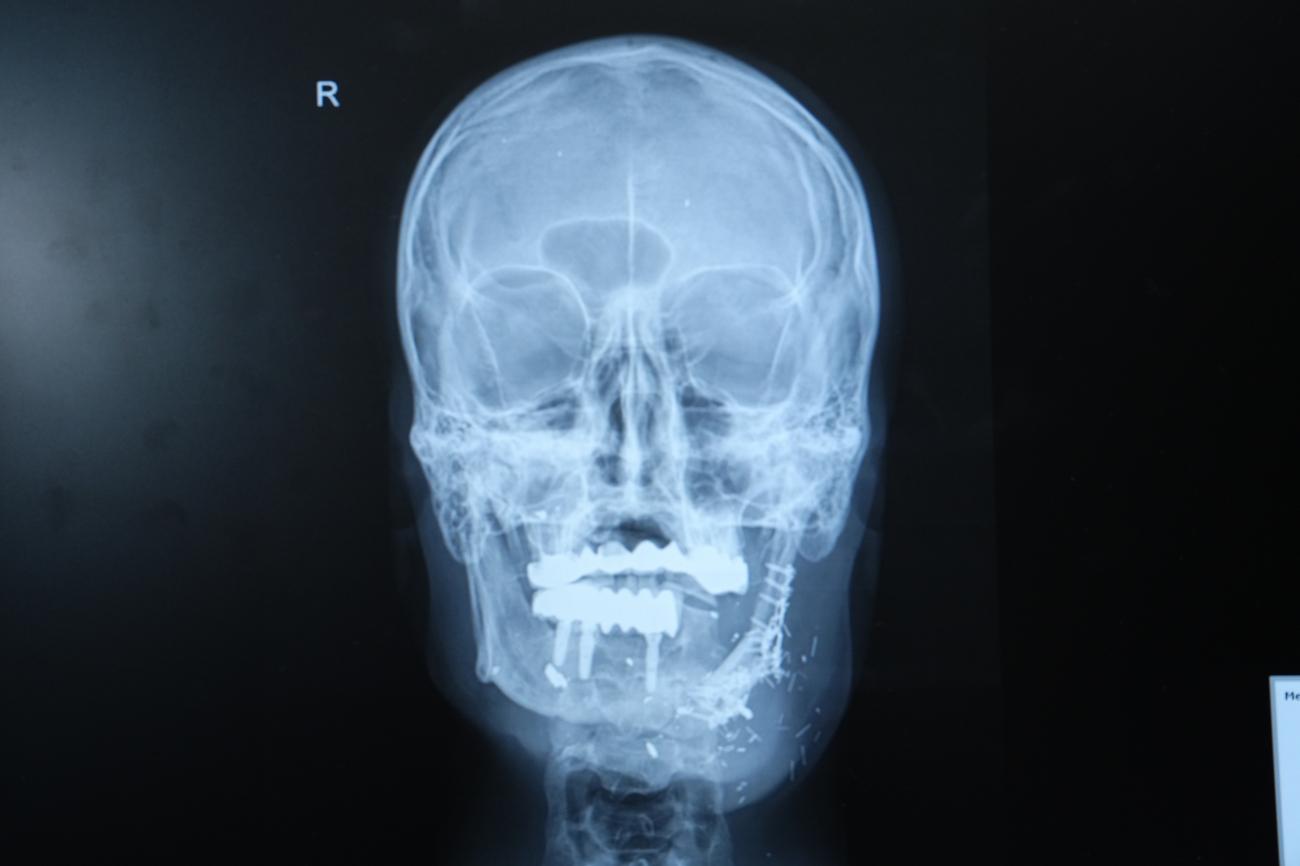

Hastanın durumunun oldukça komplike olduğunu dile getiren Doç. Dr. Özkan, "Hastamız ateşli silah yaralanması sonrası çenesinin yarısını kaybetmişti. Daha önce farklı merkezlerde ameliyat olmuş fakat nakiller başarısız olmuştu. Hem çene bütünlüğünü sağlamak hem de ileride implant yapılabilecek sağlam bir kemik dokusu oluşturmak gerekiyordu. Hastanın bacağından aldığımız kemiği mikrocerrahi yöntemle çeneye naklettik. Damarlara bağlantı yaptık, plaklarla sabitledik. Bu sayede hem fonksiyonel hem de estetik olarak başarılı bir sonuç elde ettik" diye konuştu.

Doç. Dr. Özkan, bu tür vakalarda mikrocerrahinin önemine dikkat çekerek, "Kompozit doku eksikliklerinde vasküler kemik transferi bize büyük avantaj sağlıyor. Hastamız şu an kendi beslenmesini sağlayabiliyor. Önümüzdeki süreçte kemik iyileşmesini tamamladıktan sonra diş implantları yerleştireceğiz ve hastamız çok daha rahat beslenebilecek." şeklinde konuştu.